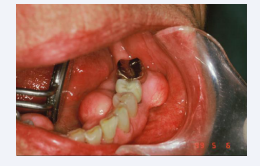

The Cupola

The most common compression NCL is a perfectly rounded depression Aka; occlusal dimples, found at the tips of functional cusps (Figure 2).

Figure 2 Occlusal dimples, found at the tips of functional cusps

Figure 2: Occlusal dimples, found at the tips of functional cusps

Nothing of significance has been written about them except that they are associated with compression. Although the cupola contrasts dramatically in geometric design with the wedge shaped NCL, there are two striking similarities, i.e., they are both site specific in that they are found at sites of high stress on teeth, and they exhibit a glassy sheen.

Kornfeld wrote about this phenomenon in 1932 when he observed that these defects were hard, smooth, and glasslike in appearance [4]. The author suggests that this glassy effect is due to the exit of positive ions produced by the compression of appetite crystals in the dentition and the alveolar bone [5], due to a piezoelectric effect. The result is a mechanical deformation due to positive ions being emitted through these focal points of high stress which explains the glassy effect and the loss of tooth structure as well. It is not unusual to find these glassy concavities on the first molars only as they appear first in the transgression from deciduous to secondary dentition and receive the full force of compression which is reduced with the emergence of the remaining dentition.